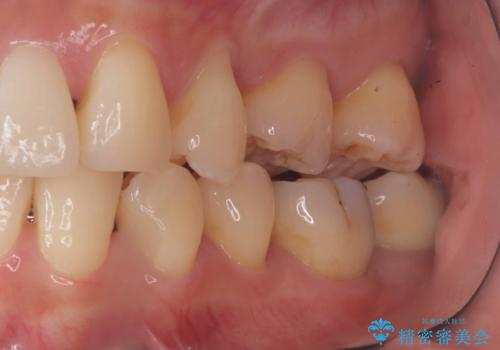

- 銀歯の下に虫歯が見つかりました。一度治療されている歯であり、レントゲン上では虫歯が神経に近い位置まで進行している様子が確認されました。

ただし、自発痛の既往はなく、歯髄診の結果も正常であったため、虫歯除去中に露髄した場合には生活歯髄療法(VPT)を行う方針としました。

実際の治療ではVPTを施行し、その後痛みなどの症状もなく経過は良好でしたので、最終的にセラミックインレーによる修復を行いました。